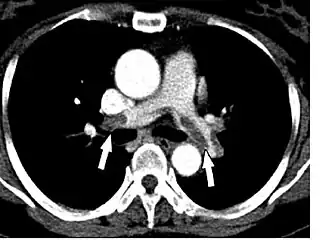

В норме КТ-ангиопульмонография демонстрирует однородное заполнение контрастным препаратом лёгочных артерий. Препятствие кровотоку в просвете сосуда визуализируется в виде «тёмного» неконтрастируемого участка (дефекта наполнения). В идеале, в момент исследования аорта не должна быть заполнена контрастным препаратом, что позволяет исключить артефакты, которые могут симулировать дефекты наполнения.